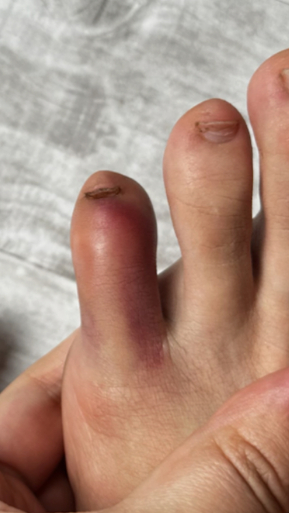

Гнойный панариций

Жалоба на резкую, пульсирующую боль, распирание, нарушение функции

Назначено: 1 процедура ФДТ REVIXAN (монотерапия)

Параметры изменяются в зависимости от процедуры

Дата публикации: 02.10.2025 15:53:58